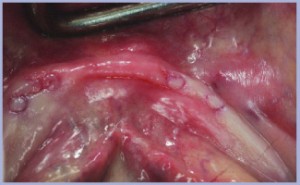

Si marca la mucosa con il mucotomo montato sul contrangolo (figg. 4-5) e si rimuovono i tasselli con l’aiuto di uno scollaperiostio (figg. 6-7). L’osteotomia, molto semplificata, prevede l’utilizzo di una fresa a pallina, in alcuni casi non indispensabile, e della fresa pilota diametro 2,2 mm. Dopo aver controllato il parallelismo con i pin (fig. 8) si prelevano i monoimpianti dalla loro confezione, il tappo-avvitatore di plastica sul quale sono montati consente l’inserimento iniziale. Nel momento in cui il tappo-avvitatore non permette di proseguire l’avvitamento del monoimpianto, l’operatore avverte che il tappo gira a vuoto, l’operazione deve essere completata con l’ausilio dell’apposita chiave a farfalla. Dopo aver inserito i quattro monoimpianti (fig. 9) si rilevano un morso di centrica in silicone (Fig. 10) e un’impronta della protesi antagonista (fig. 11). Si posizionano le quattro cuffie standard sui monoimpianti (fig. 12) che rimangono incluse, insieme alla protesi preesistente, in una impronta di posizione (fig. 13). Il laboratorio ha provveduto nella stessa giornata all’inserimento dei denti mancanti mantenendo lo spazio necessario all’alloggiamento delle cuffie (fig. 14). Per alcuni giorni la paziente ha utilizzato la protesi con le cuffie inserite sui monoimpianti ma non ancora bloccate alla protesi con lo scopo di ottenere un corretto appoggio mucoso.

- Fig.3

- Fig.4

- Fig.5

- Fig.6

- Fig.7